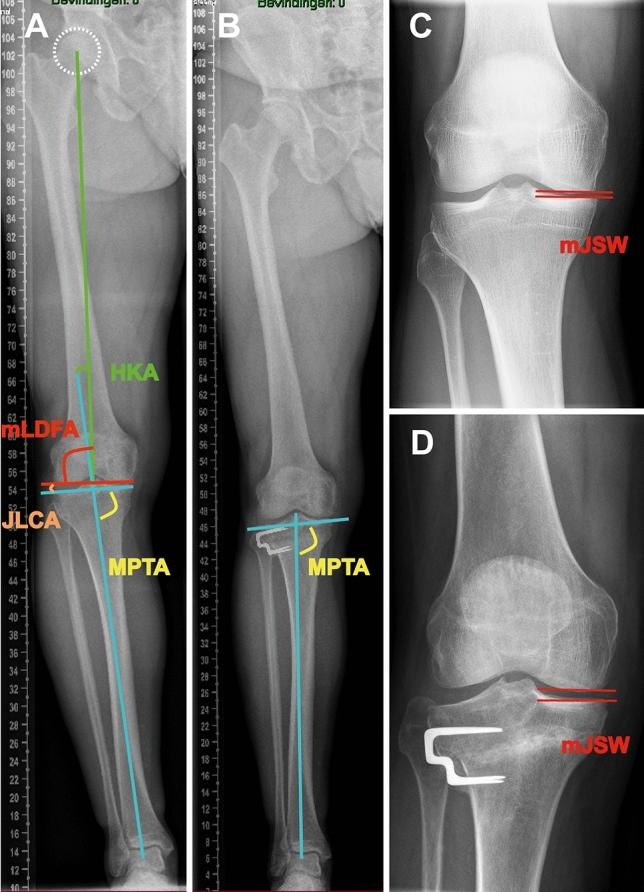

METHODS

A cohort of 180 patients treated in one single hospital with lateral closing-wedge HTO was examined. KJLO was defined by the medial proximal tibial angle (MPTA). To assess the association between KJLO and patient-reported outcome, radiological progression of osteoarthritis, and surgical survival, patient groups were defined: I, postoperative MPTA < 95.0°; II, postoperative MPTA ≥ 95.0°; A, MPTA change < 8.0°; B, MPTA change ≥ 8.0°. Propensity score matching was used for between-groups (I and II, A and B) covariates matching, including age, gender, preoperative lower limb alignment, preoperative medial joint space width (mJSW), preoperative Western Ontario and McMaster Universities osteoarthritis Index (WOMAC) score, wedge size, and postoperative follow-up time. Patient-reported outcome was assessed by the WOMAC questionnaire, radiological progression of osteoarthritis by mJSW and Kellgren-Lawrence (KL) grade progression (≥ 1) preoperatively and at follow-ups (> 2 years). Failure was defined as revision HTO or conversion to knee arthroplasty.

方法

对在一家医院接受外侧闭合楔形 HTO 治疗的 180 例患者进行了检查。KJLO 通过内侧胫骨近端角(MPTA)来定义。为了评估 KJLO 与患者报告的结果、骨关节炎的放射学进展以及手术生存率之间的关系,将患者分为以下几组:I 组,术后 MPTA<95.0°;II 组,术后 MPTA≥95.0°;A 组,MPTA 变化<8.0°;B 组,MPTA 变化≥8.0°。使用倾向评分匹配进行组间(I 组和 II 组、A 组和 B 组)协变量匹配,包括年龄、性别、术前下肢对线、术前内侧关节间隙宽度(mJSW)、术前西部安大略省和麦克马斯特大学骨关节炎指数(WOMAC)评分、楔形大小和术后随访时间。通过 WOMAC 问卷评估患者报告的结果,通过 mJSW 和 Kellgren-Lawrence(KL)分级进展(术前和随访时≥1)评估骨关节炎的放射学进展(>2 年)。失败定义为翻修 HTO 或转换为膝关节置换术。